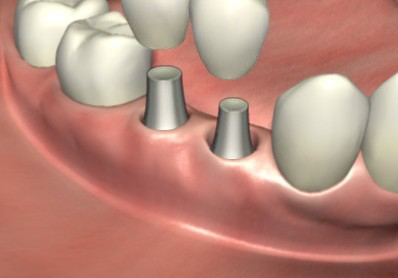

ЁЁЁЁ4ЁЂШэзщжЏГЩаЮКѓгУгРОУЛљЬЈЛЛЯТгњКЯЛљЬЈЃЌНЯКѓАВзАЙЬЖЈжжжВбРЙкБуЭъГЩСЫжжжВбРЪжЪѕЁЃ